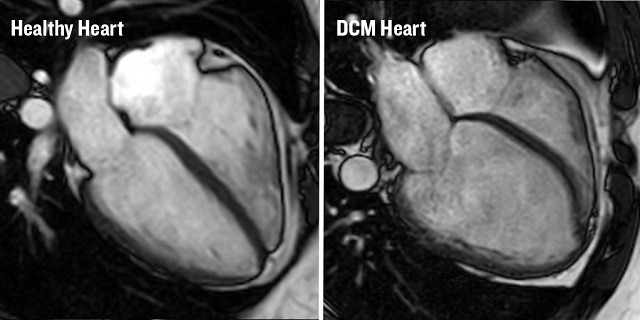

DCM is a condition that stretches and thins the heart muscle so it becomes ‘baggy’ and is unable to pump blood around the body efficiently. It is estimated to affect up to 260,000 (1 in 250) people in the UK and is the leading cause of heart transplantation.